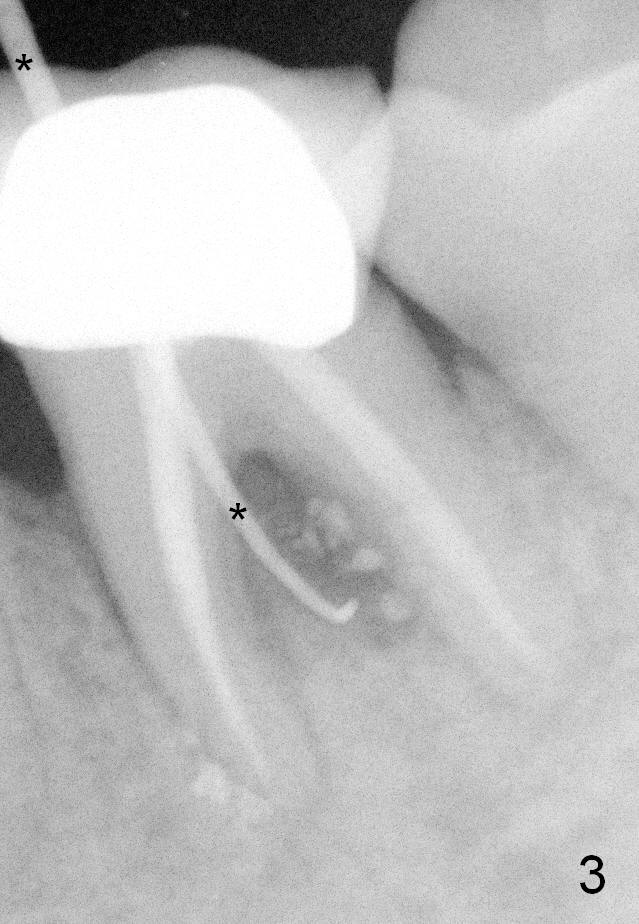

A 59-year-old lady has history of periodontal disease and bruxism.  The tooth #19 has pulpitis after unsuccessful DO composite (Fig.1 *) and requires root canal therapy (Fig.2).  Six months later, a fistula is found to communicate with the furca (Fig.3 *: gutta percha).  Less than 3 years, the furca enlarges with symptoms of infection (Fig.4 *).  She works out of state. The Principle of No Implant, No Extraction is adhered.  Since she is of short statue, the bone height is relatively limited.  A 6x14 mm tissue-level implant is appropriate (Fig.5, one piece).  Sensor 1 may be proper for her small mouth.  When the bottom of the socket is large and close to the Inferior Alveolar Nerve, can an immediate implant be placed?